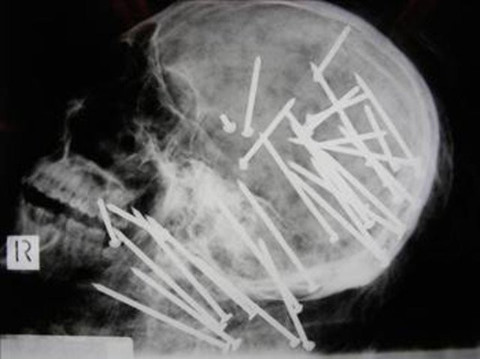

Galerinin tamamı için tıklayınız27 yaşındaki Chen'in cesedini inceleyen uzmanlar, büyük şok yaşadı. Chen'in kafatasının röntgeni çekildiğinde kafasına bir sürü çivi çakılmış olduğu görüldü. İncelemeden sonra Chen'in çivi tabancası ile öldürüldüğü anlaşıldı.